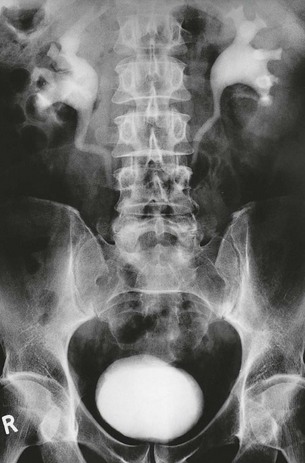

Fig. 39.4 Horseshoe kidney

Horseshoe kidney shown on IVU from a 51-year-old woman with recurrent urinary tract stones; the pelvicalyceal systems are oriented obliquely and converge inferiorly because the isthmus is stretched over the vertebral column. Each pelvis and ureter is more medially placed than normal and the whole renal mass lies much lower than would normal kidneys. The isthmus of a horseshoe kidney can rarely be demonstrated by IVU or ultrasound but can easily be imagined in this image